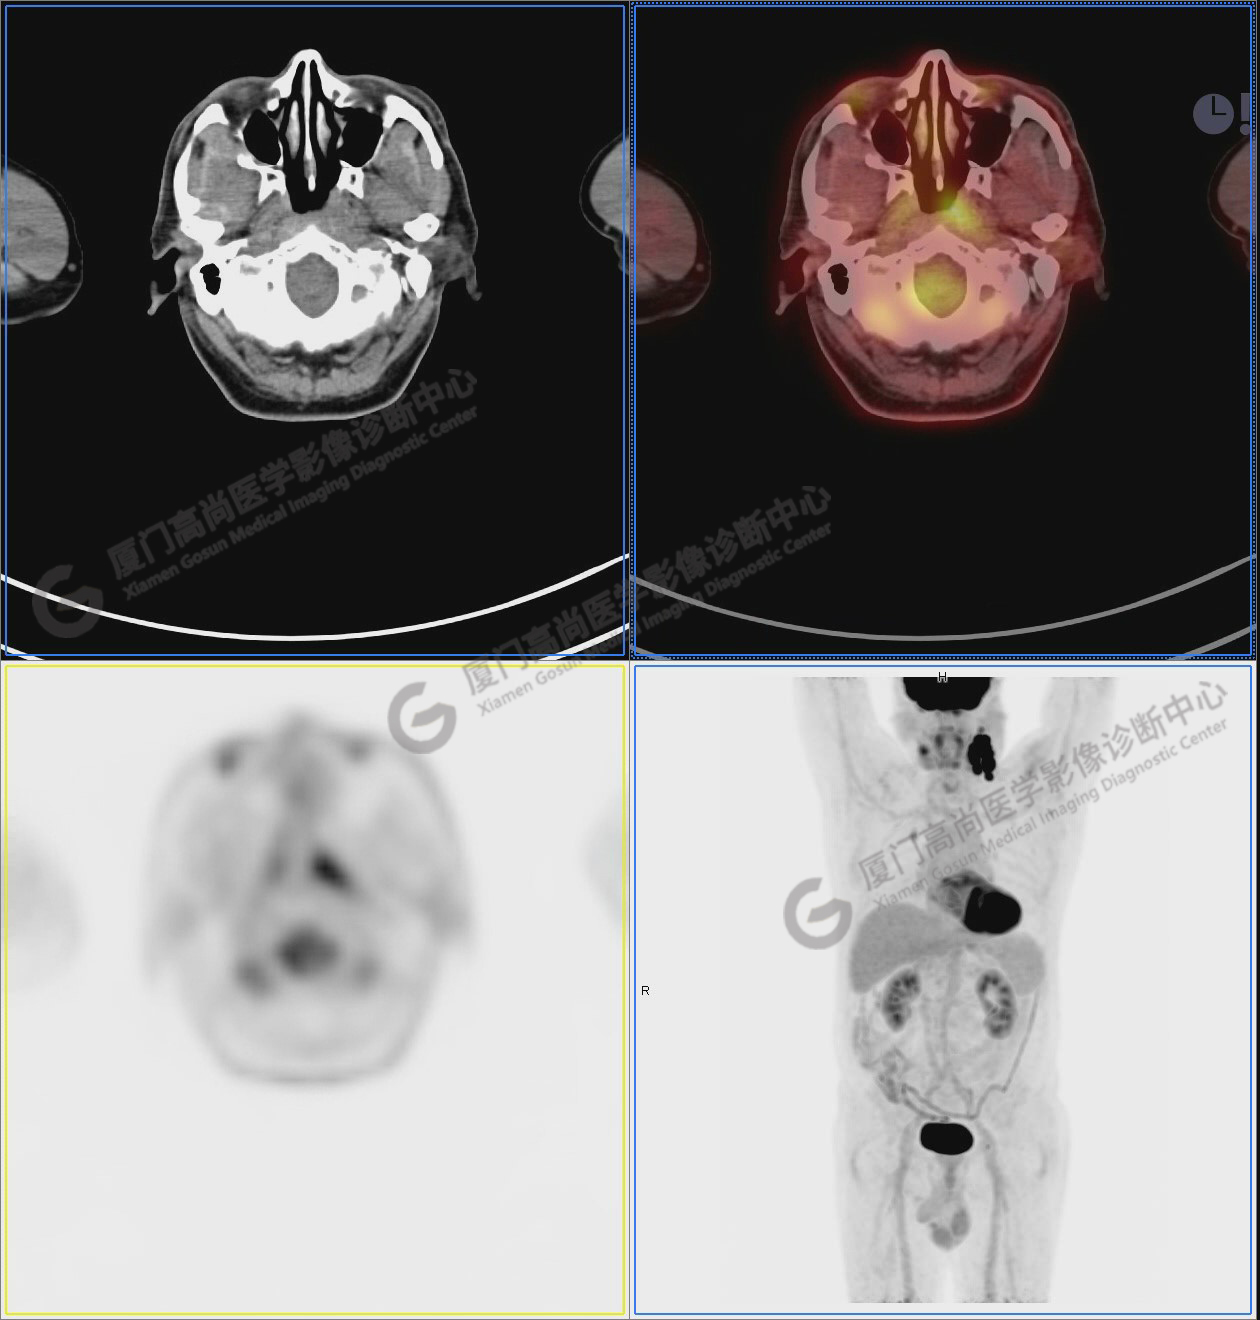

圖6-9:鼻咽左側(cè)壁增厚,代謝異常增高,考慮為鼻咽癌

圖6

圖7

圖8

圖9